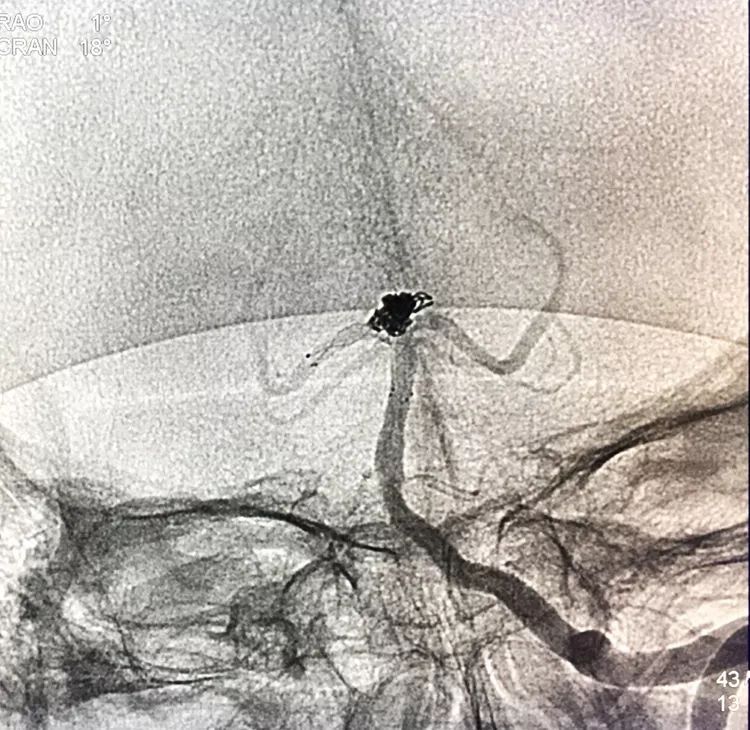

回到工作位造影,显示基底动脉顶端动脉瘤完全栓塞,基底动脉顶端四根血管畅通。

术后左椎动脉正位、侧位的造影和蒙片

挠痒挠个正着,舒服!